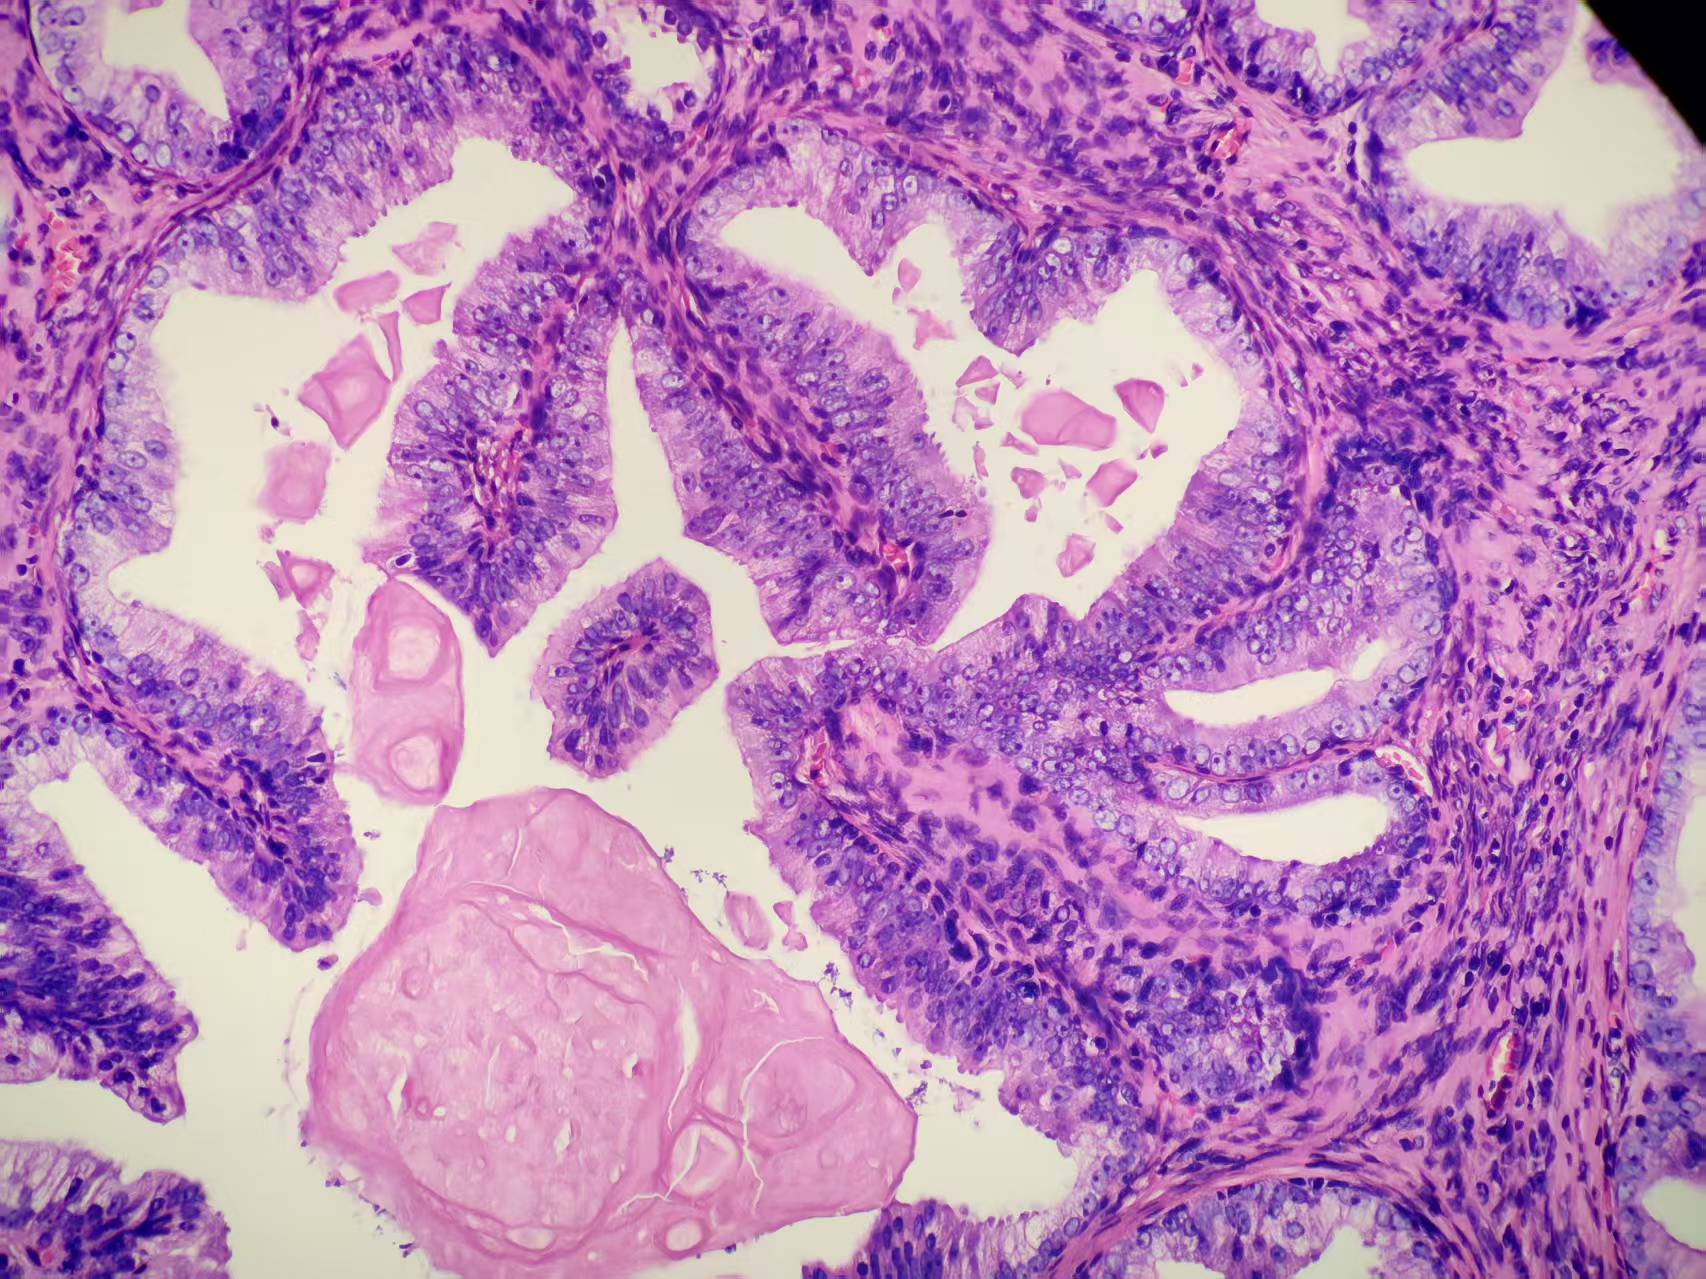

前列腺PIN?

发现肉眼血尿5月余,PAS 5.7

经尿道前列腺等离子电切组织

本例核仁巨大,值得关注!

嗜酸性大核仁,胞浆透亮,PIN没问题。还是组化一下吧,

zhuang xia nan:

标记一下,除外更重病变。